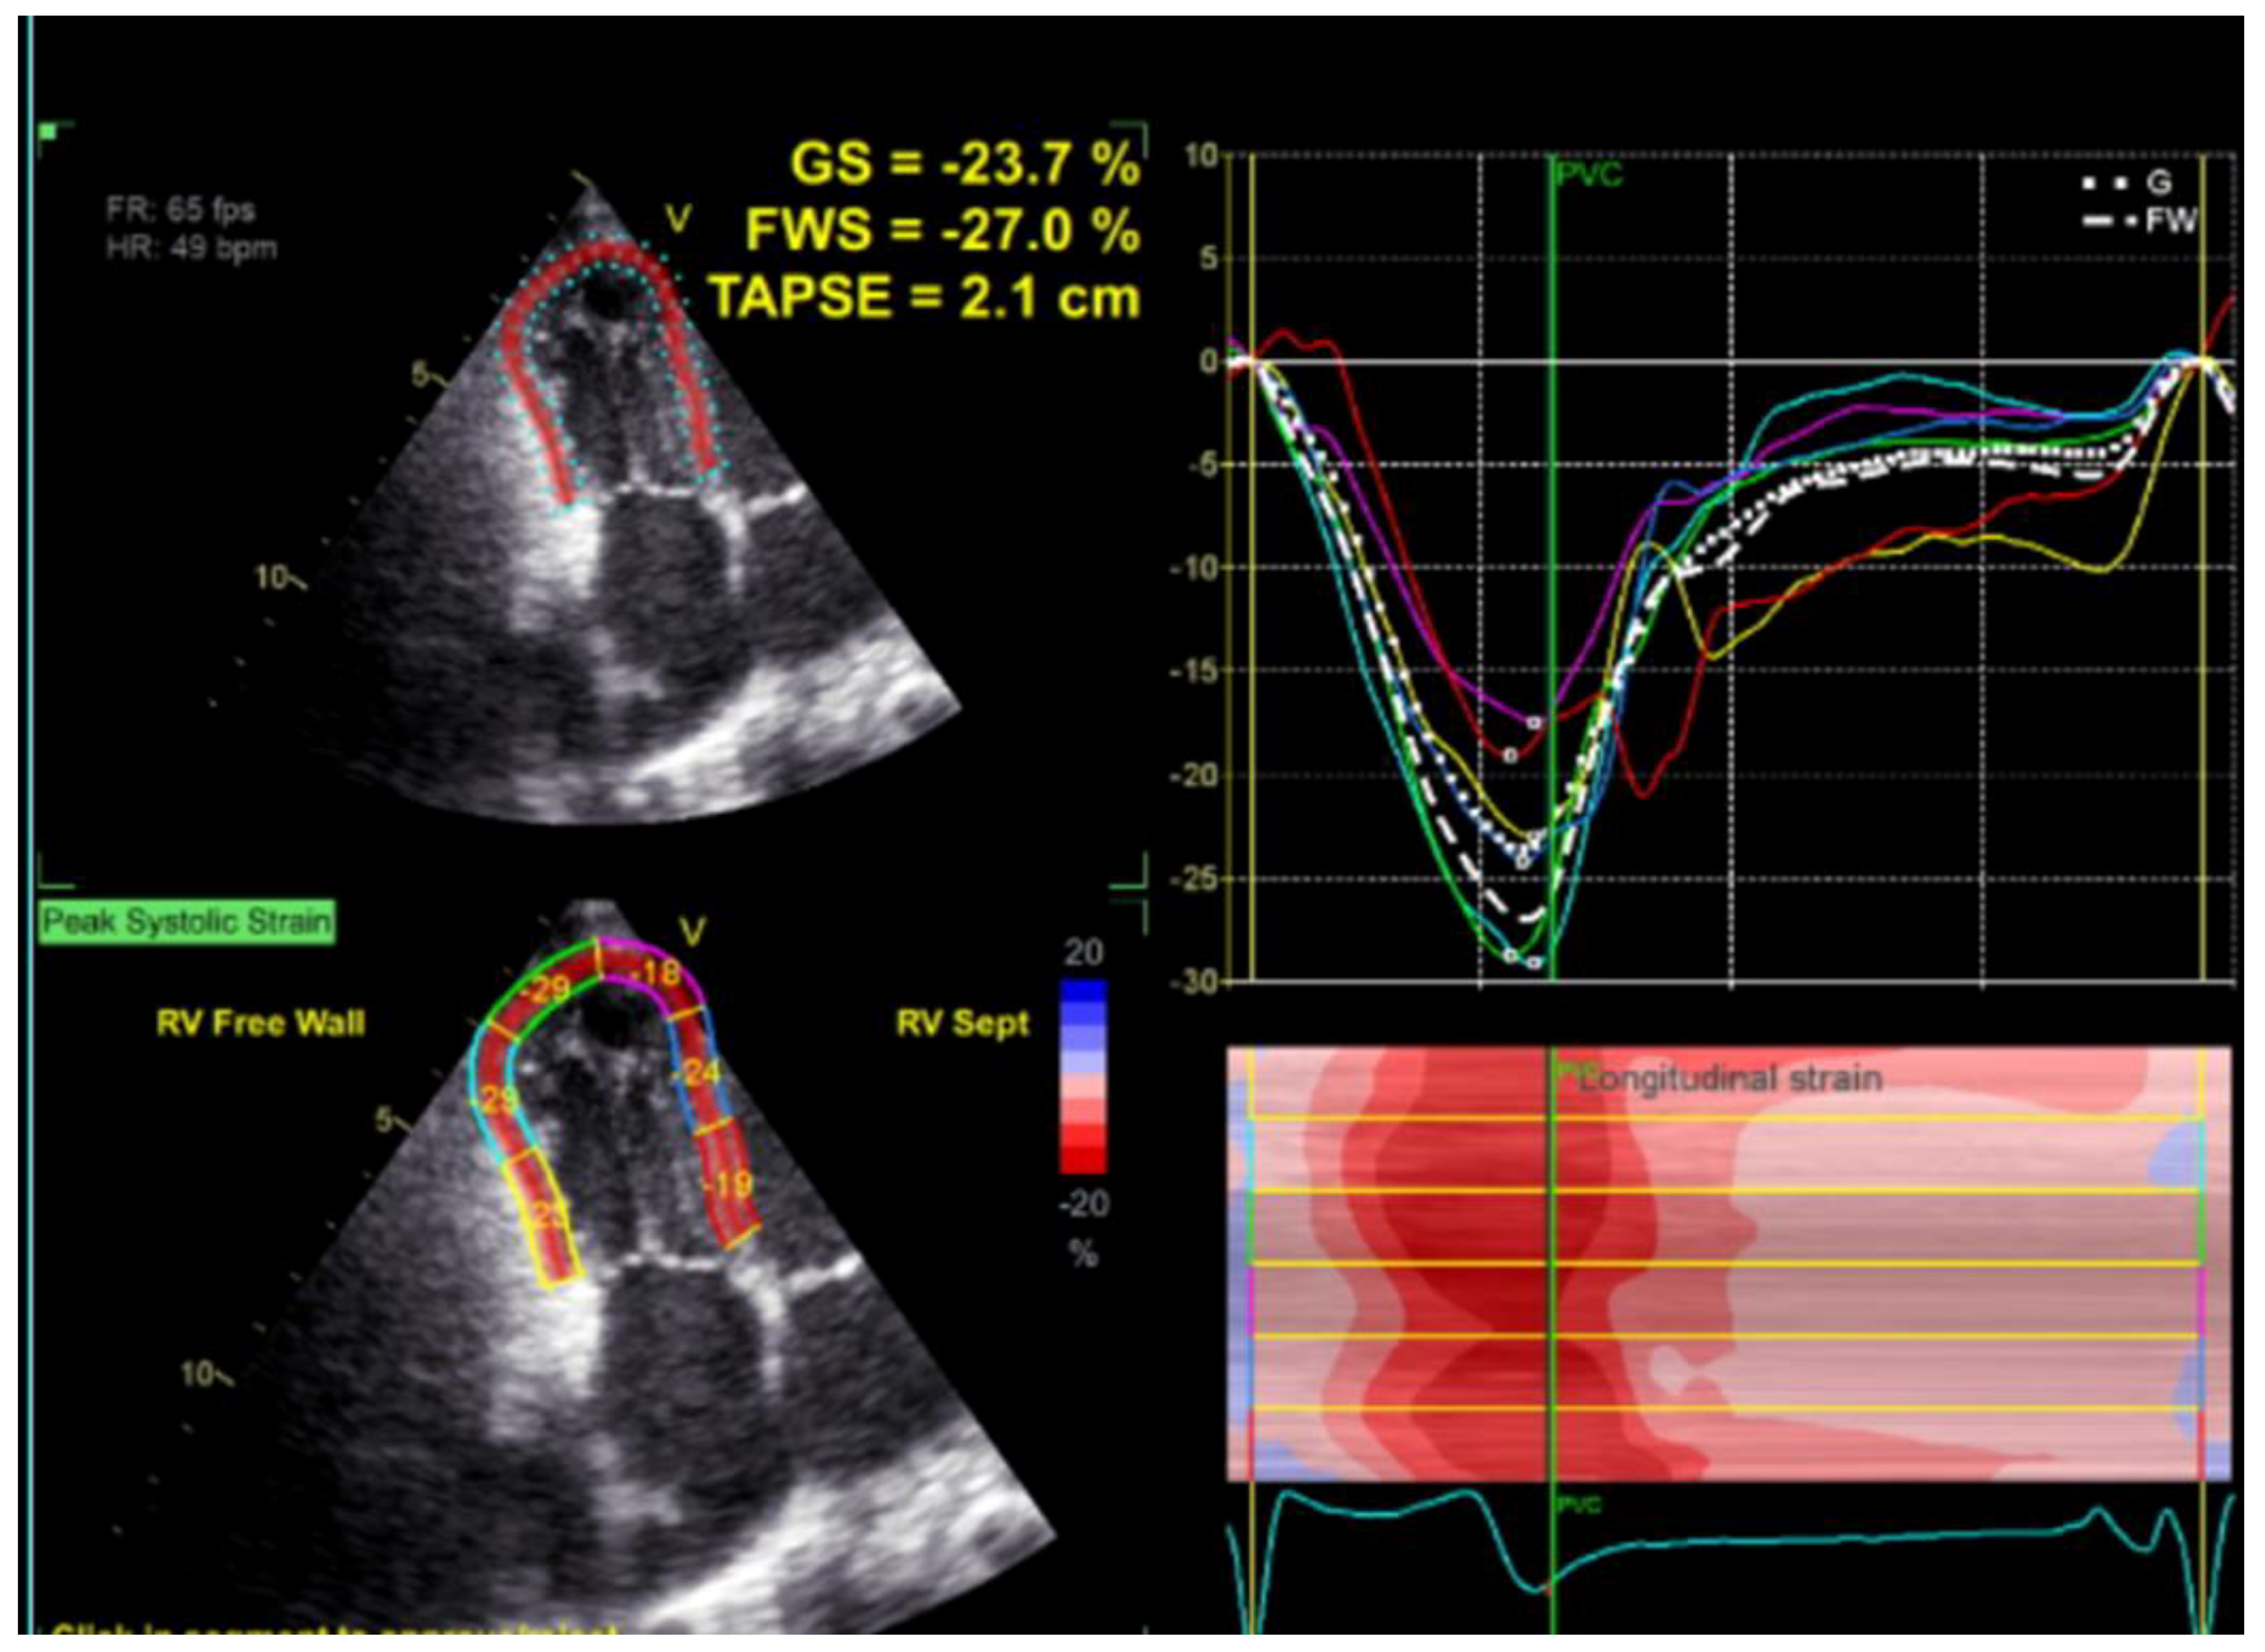

| TAPSE | Tricuspid Annular Plane Systolic Excursion |

| GS | Global Strain |

| FWS | Free Wall Strain |